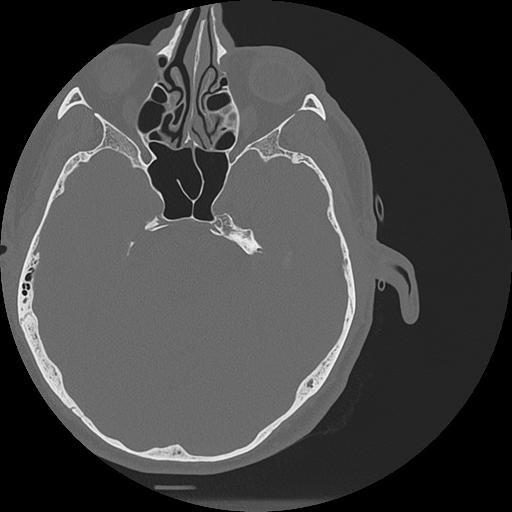

7 HUESO,,Vol,0.5,HUESO,,